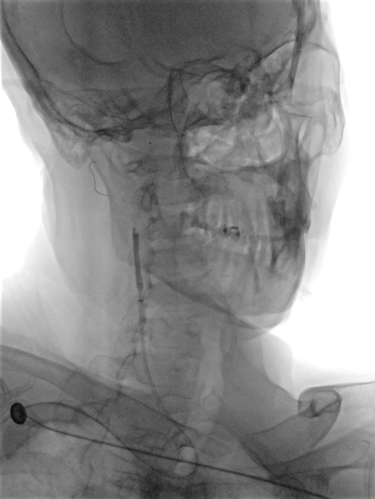

桡动脉入路行DSA:右侧颈内动脉C1段重度狭窄。

右侧桡动脉穿刺,置入7F薄壁鞘,造影示右侧颈内动脉C1段重度狭窄,狭窄率约90%,狭窄长度约22mm。通过加硬泥鳅导丝、125cm SIM2造影导管辅助,将5.5F Introsky X导管鞘置于右侧颈总动脉远端,选择KangFly微导丝携带Spider FX保护伞通过狭窄病变后释放保护伞,5.0*30mm球囊预扩张,置入9*40mm自膨式支架。

术后即刻影像:造影见右侧颈内动脉C1段血流通畅,mTICI3级。